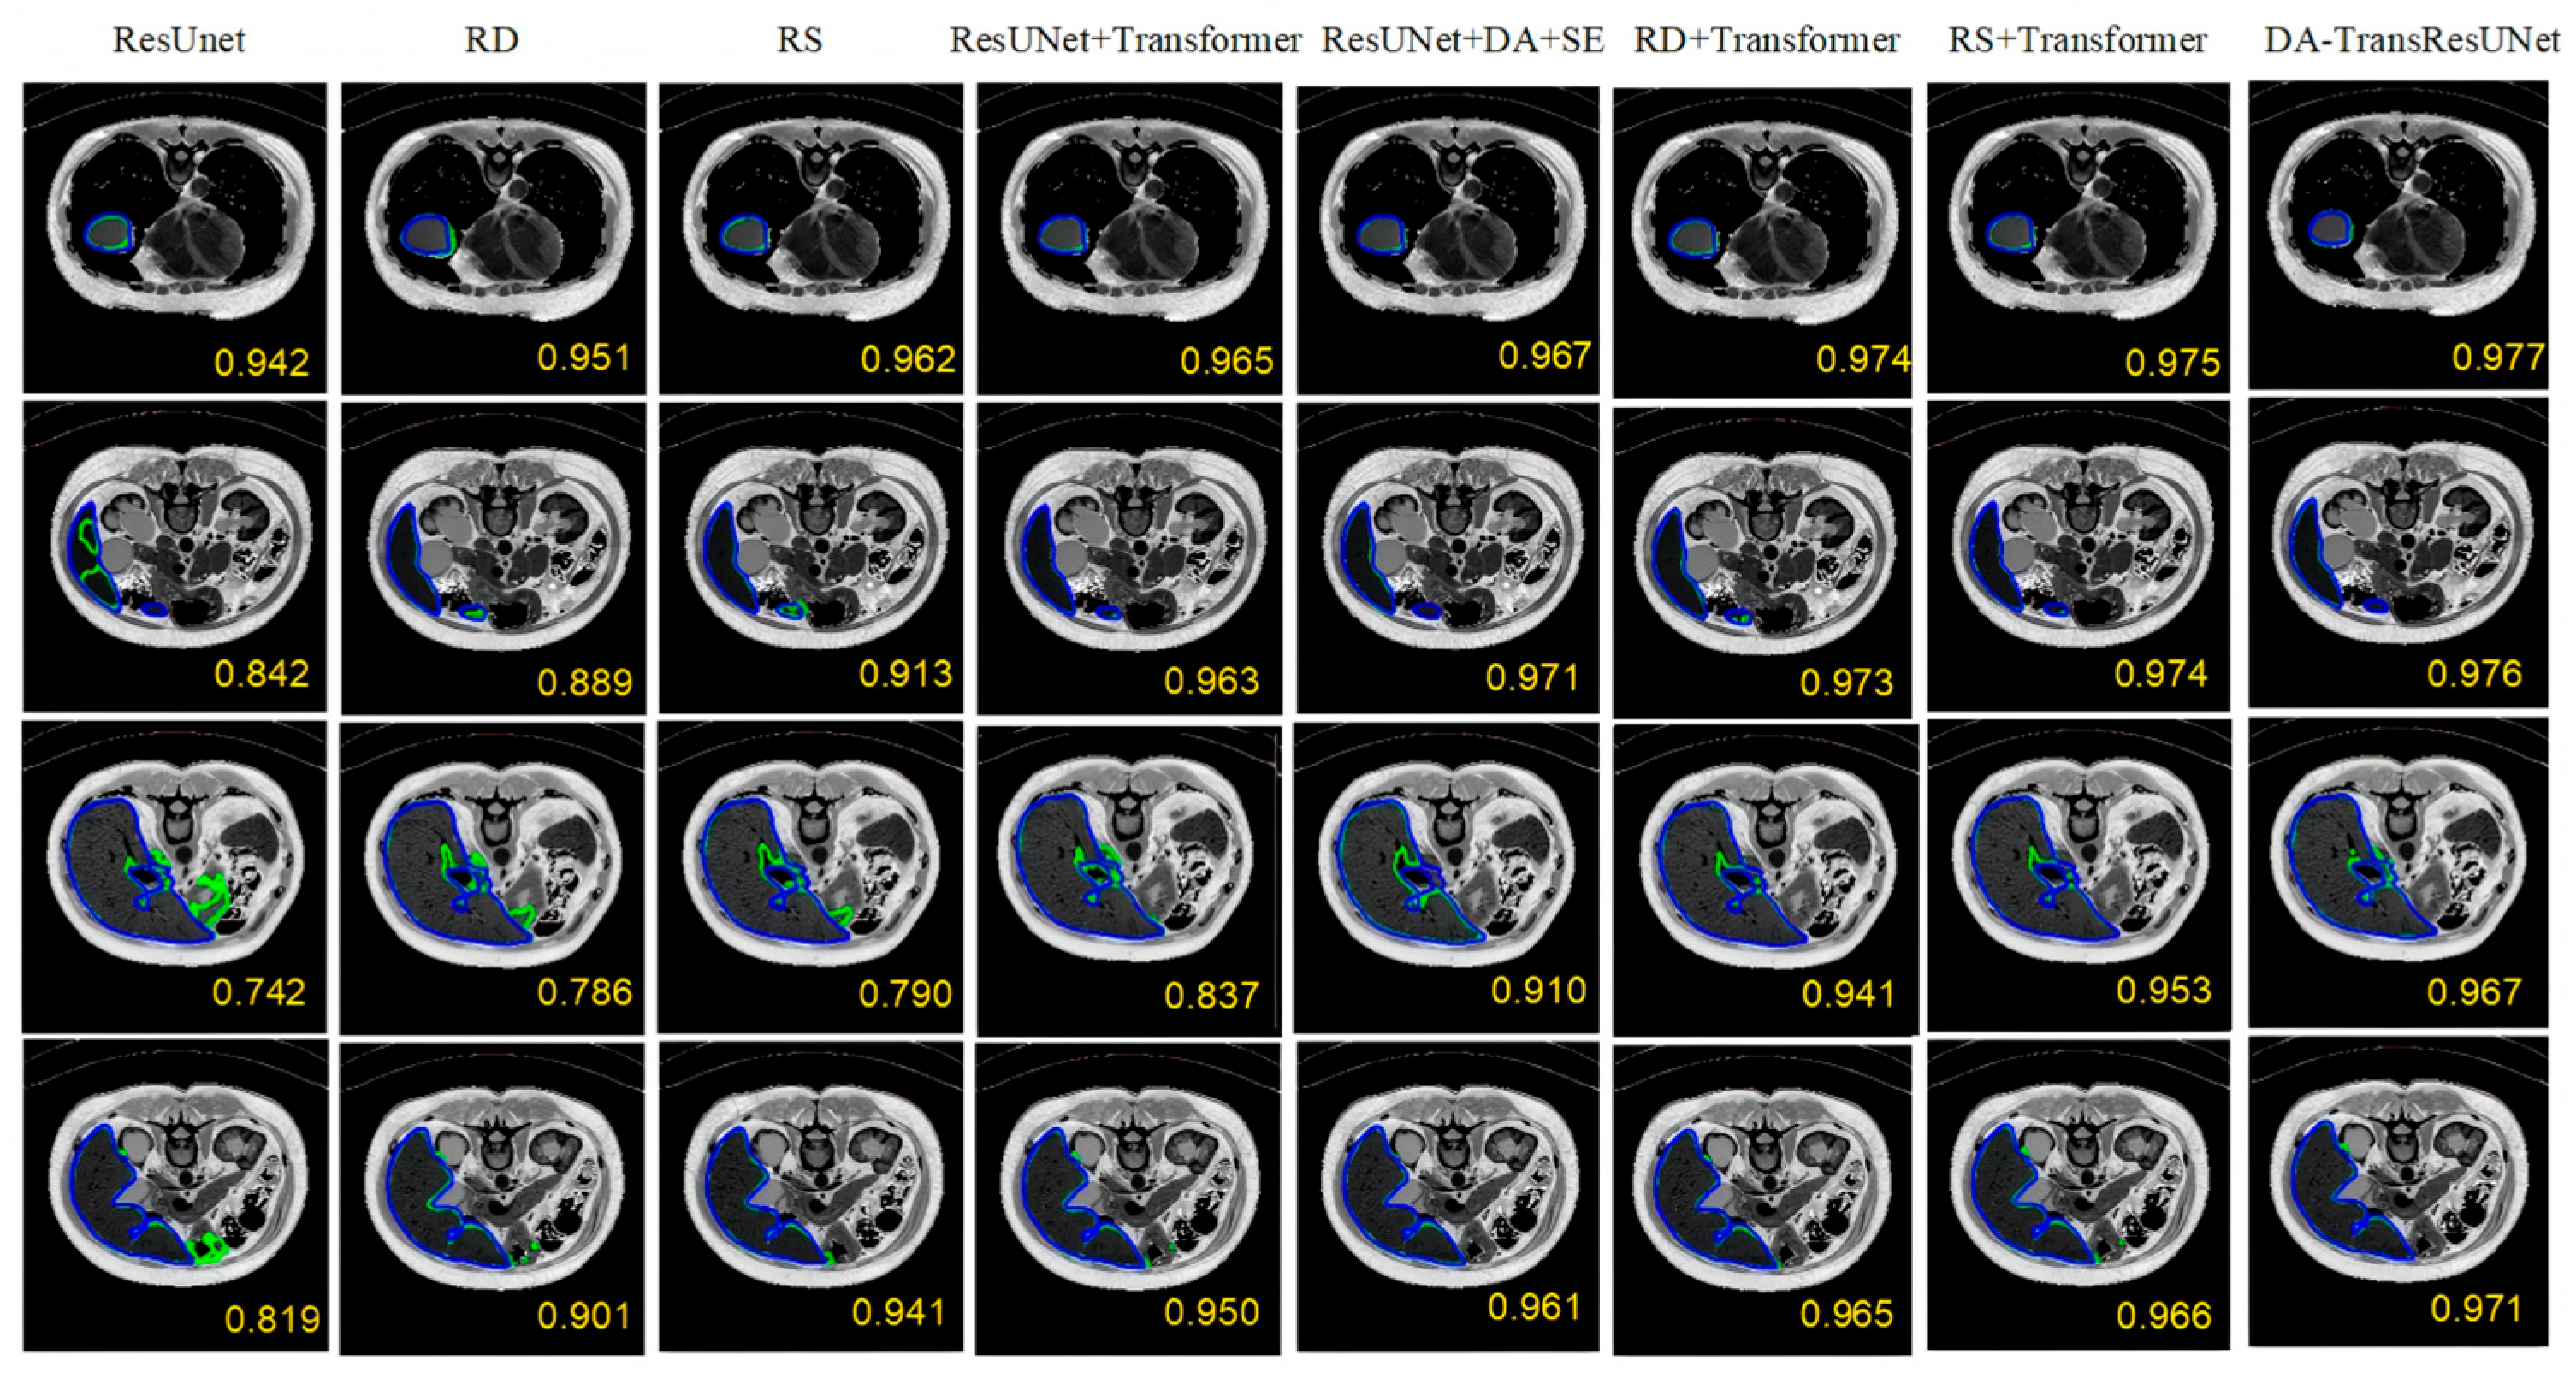

5.1. Ablation Experiment

| Model | DICE (%) | VOE (%) | RVD (%) | ASD (mm) | MSD (mm) |

|---|---|---|---|---|---|

| Res U-Net | 96.93 | 9.84 | −2.78 | 8.06 | 46.11 |

| ResU-Net + DA | 97.39 | 7.86 | 1.31 | 8.10 | 38.49 |

| ResU-Net + SE | 97.59 | 7.7 | −1.66 | 8.11 | 39.83 |

| ResU-Net + Transformer | 97.64 | 8.99 | −1.88 | 8.03 | 38.12 |

| ResU-Net + DA + SE | 97.67 | 7.62 | −0.95 | 8.02 | 38.70 |

| ResU-Net + DA + Transformer | 97.74 | 7.55 | −1.10 | 7.99 | 37.90 |

| ResU-Net + SE + Transformer | 97.76 | 7.48 | −1.25 | 7.98 | 37.80 |

| DA-TransResUNet | 97.79 | 7.52 | −1.02 | 7.97 | 37.58 |

| Res U-Net | 83.53 | 24.97 | −7.61 | 13.88 | 155.50 |

| ResU-Net + SE | 83.87 | 19.13 | 5.19 | 11.36 | 149.04 |

| ResU-Net + Transformer | 86.19 | 17.79 | 4.65 | 9.73 | 138.61 |

| ResU-Net + DA | 86.87 | 16.72 | 3.16 | 9.69 | 101.43 |

| ResU-Net + DA + SE | 87.35 | 16.10 | 2.45 | 9.42 | 100.10 |

| ResU-Net + SE + Transformer | 88.30 | 16.35 | 2.10 | 9.05 | 105.40 |

| ResU-Net + DA + Transformer | 89.62 | 15.55 | 1.85 | 8.92 | 99.20 |

| DA-TransResUNet | 91.79 | 15.17 | 1.10 | 8.45 | 98.51 |